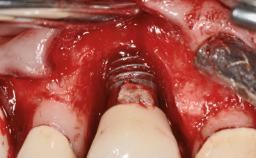

Excess Cement Resulting in Peri-implant Infection Presenting as a Draining Sinus Tract

Biological complications caused by undetected cement residue have been receiving much attention. Excess cement might be responsible not only for rapidly developing of peri-implantitis, but also for delayed or chronic manifestations of the disease many years after cementation (Wilson 2009; Linkevicius and coworkers 2013). Invitro and clinical studies have shown that it is very difficult or even impossible to completely clean up excess cement at subgingival margins, so popular in cemented restorations (Agar and coworkers 1997; Linkevicius and coworkers 2011, 2012). Possible outcomes of biological complications due to excess cement range from temporary inflammation of the peri-implant soft tissues without any serious esthetic and functional consequences all the way to implant loss. This report describes a case of peri-implantitis caused by residual cement; as well as the management and quite unusual resolution of the complication. The patient presented in 2009 with a draining sinus tract, tenderness on chewing, and tissue contact above the implant-supported restoration. The implant had been restored approximately three years before.